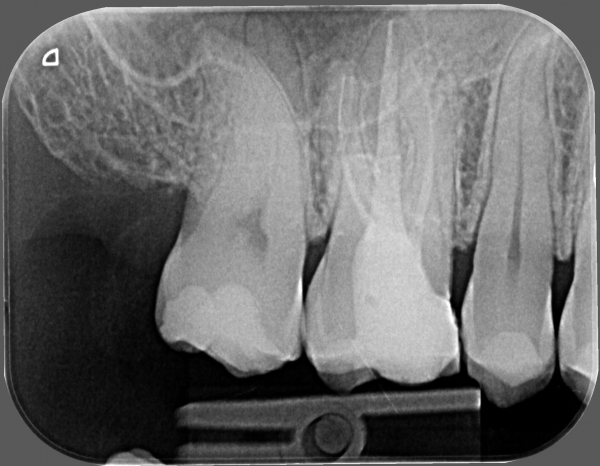

Правая верхняя 6-ка без нерва, с запломбированными каналами (уже лет 10). Вокруг нее такое ощущение, что десна зудит, уже около двух лет. Началось после смены пломбы. В последний раз на приеме доктор искала, там хоть что нибудь. Заодно проверяла зуб, под десной было очень приятное ощущение. Так же хорошо чесать нитью. Мой стоматолог не смогла ничего предположить.

Прикрепленые фото

Необходим осмотр. Следует заменить пломбу на ортопедическую конструкцию, коронку. Так как нет плотного контактного пункта между зубами, и при жевании постоянно в межзубной промежуток попадает пища, что вызывает неприятные ощущения.